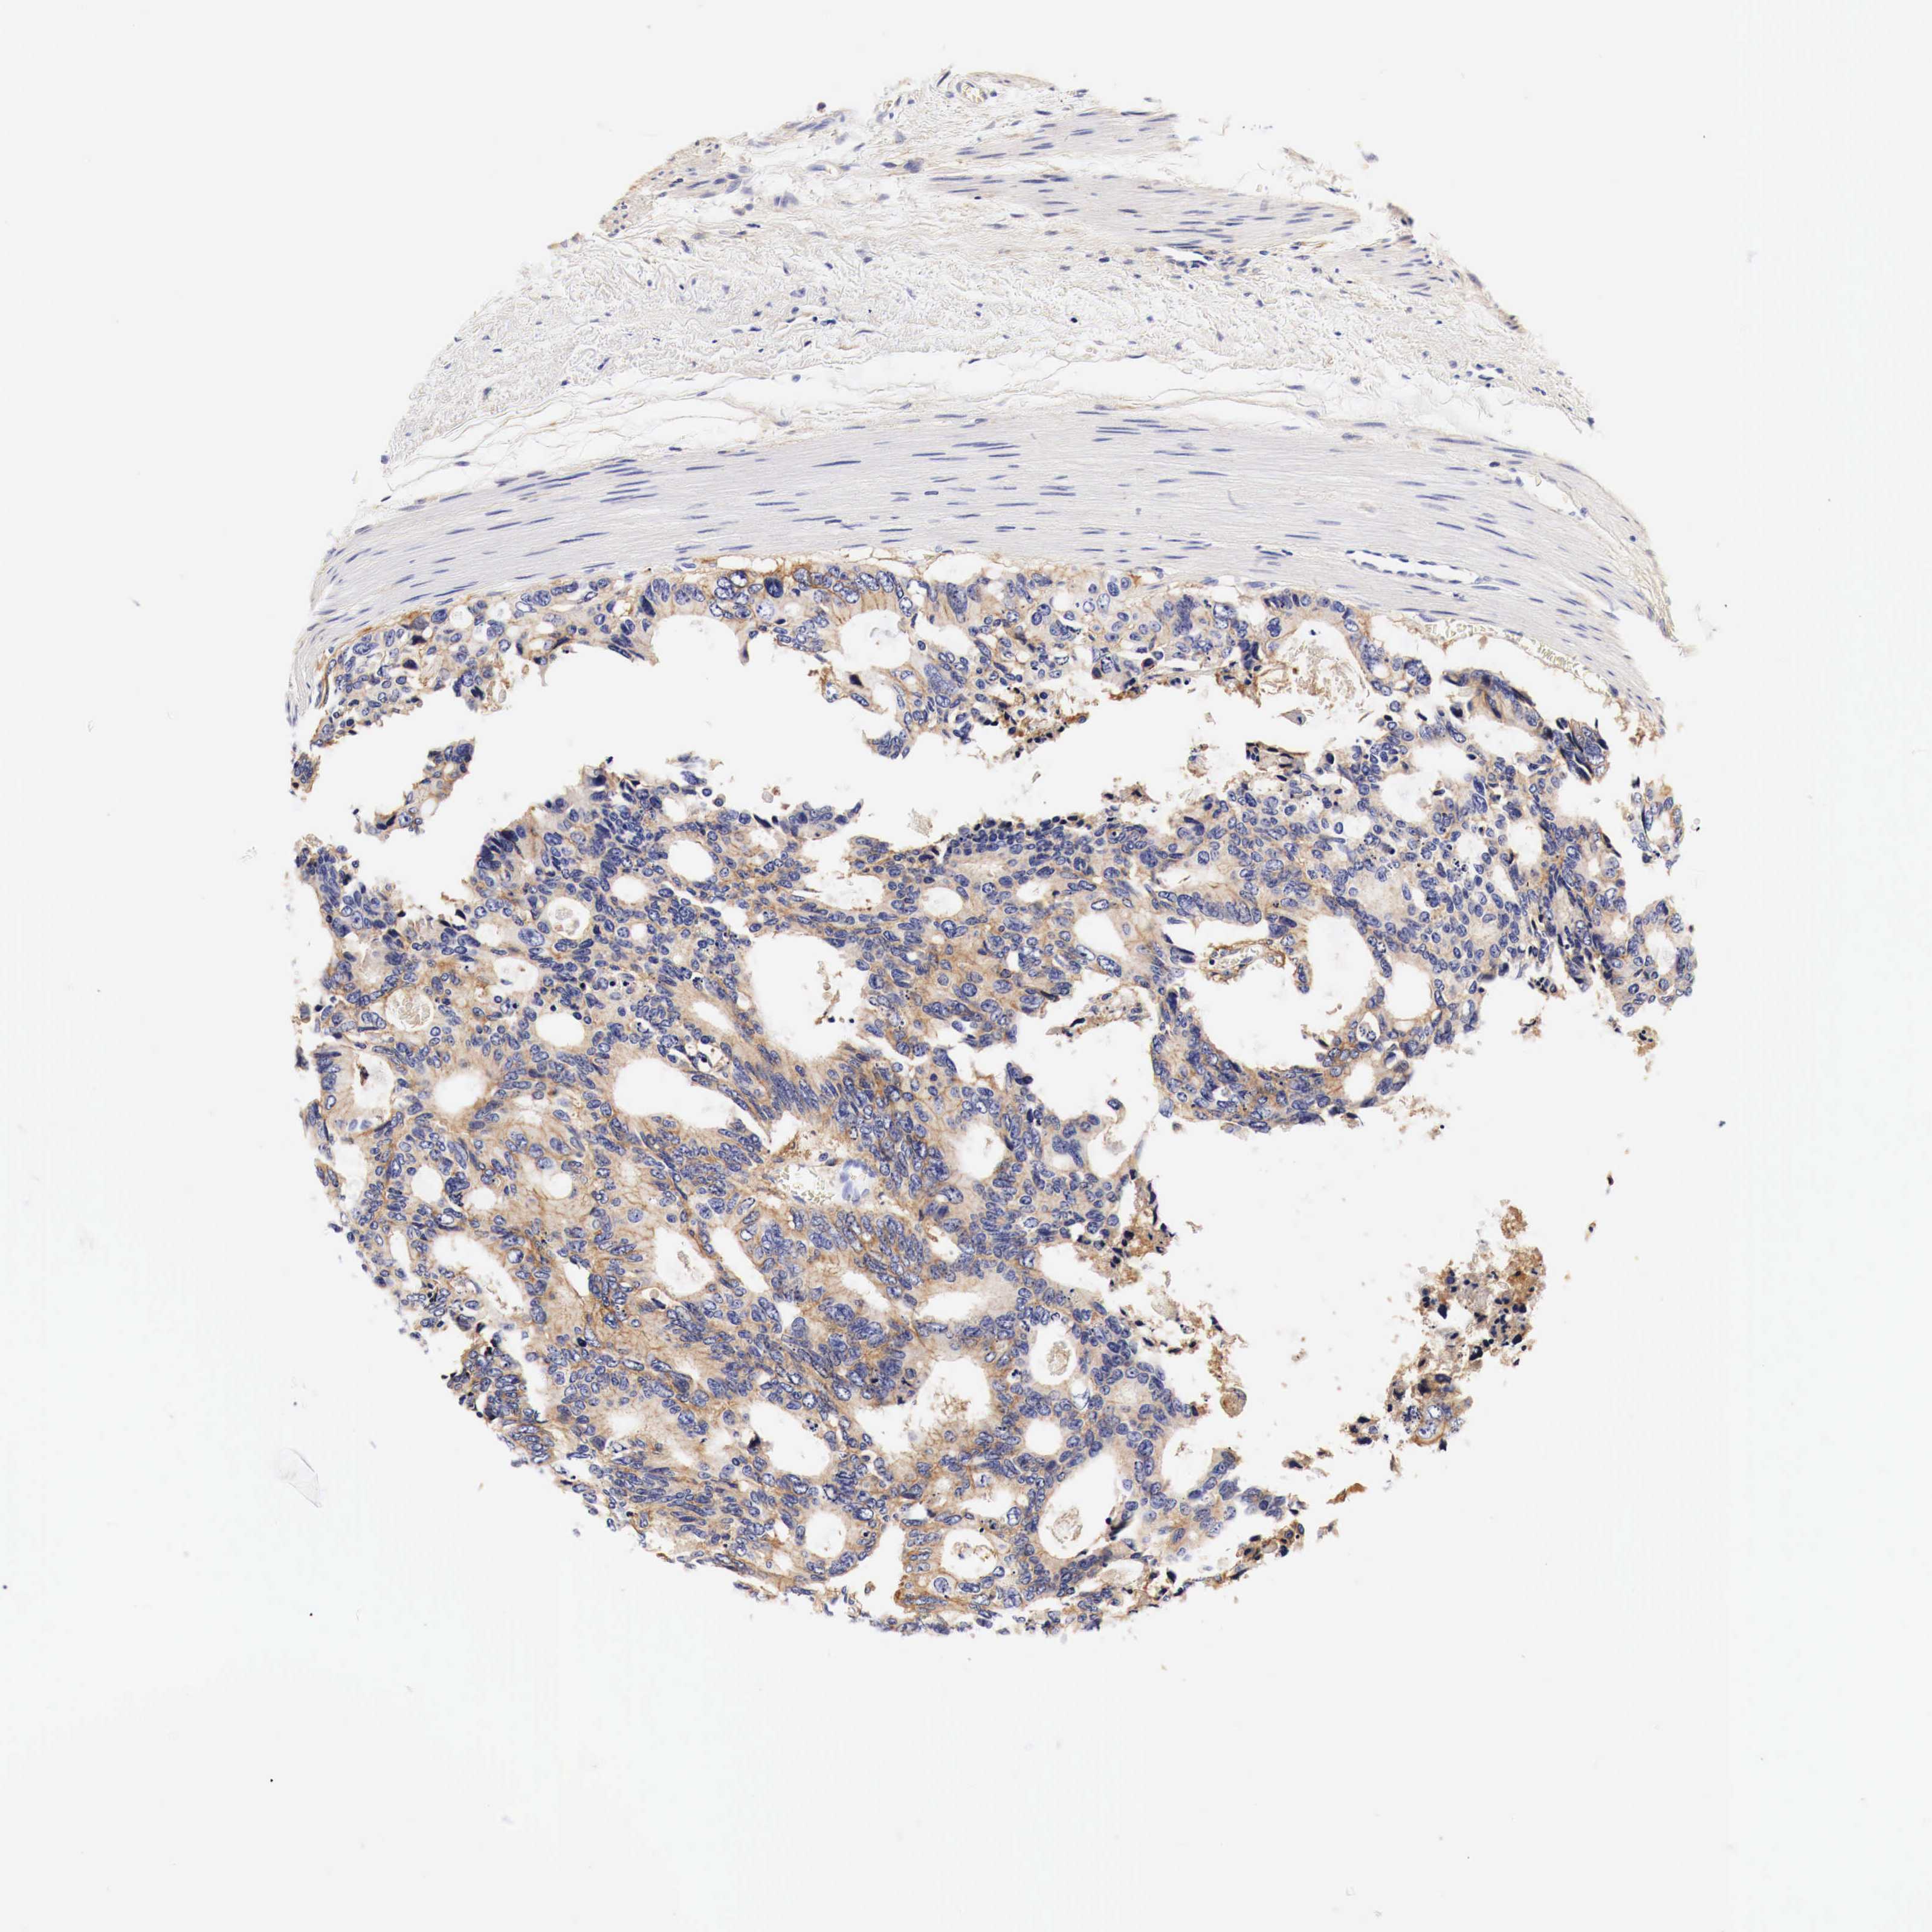

CANCER COLORECTAL CANCER Show tissue menu

Colorectal cancer

Human cancer

Colon adenocarcinoma